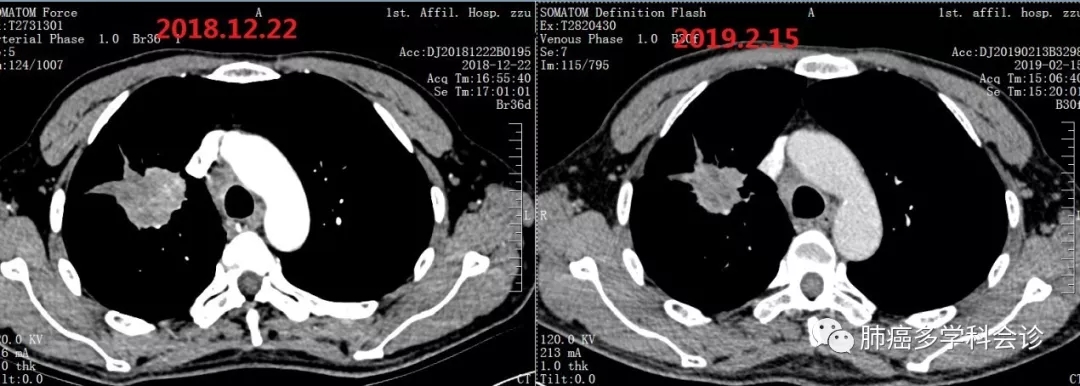

于2018-9-10 开始“培美曲塞+顺铂”化疗,共 4周期,肿瘤没有明显变化,评价疗效:SD。化疗致严重消化道反应,曾呕吐出咖啡色液体(可能系口服非甾体类止痛药及严重呕吐引起胃出血),体重下降5kg。2018-12复查CT提示疾病进展。PS 2-3 分

患者参加研究者发起的临床试验,于2018.12.27开始静脉滴注国产PD-1抗体(SHR1210),每次200mg。自诉第一周期治疗后食欲增加、下床活动明显增多。经 2周期治疗后,复查CT显示病灶较前减小:

3.webp.jpg11.webp.jpg治疗4个周期后复查,原发灶较前有所增大: